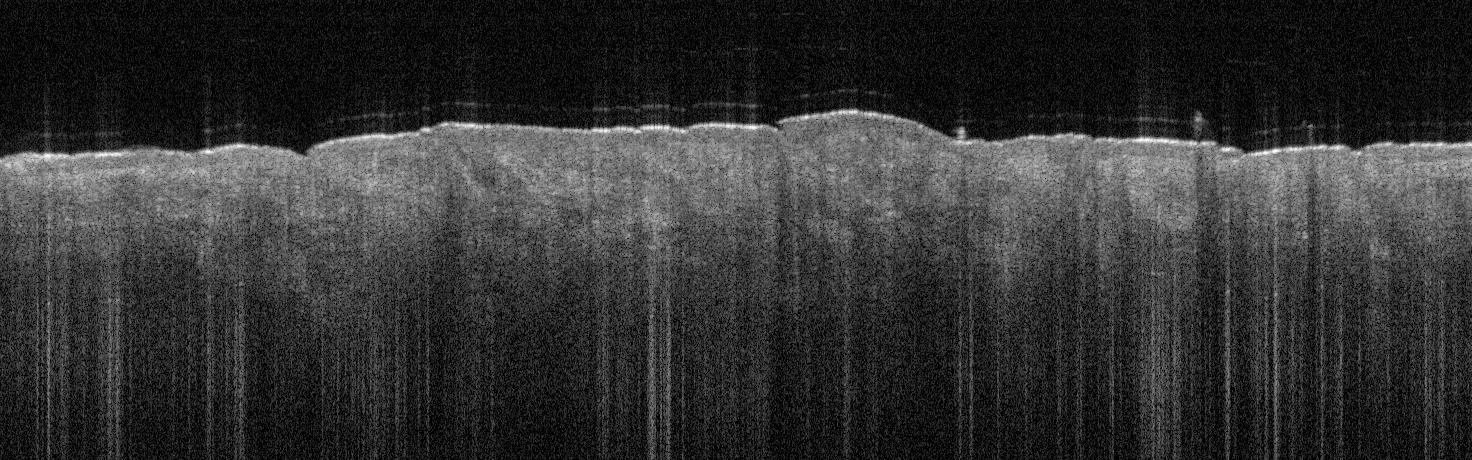

VA54: Left Superior Temple, Basal Cell Carcinoma, Nodular

- * denotes area of liquifactive necrosis with remnant necrotic cell debris